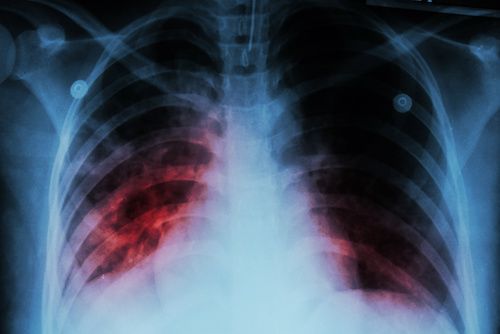

Researchers from the Julius Center for Health Sciences and Primary Care at the University Medical Center in Utrecht, The Netherlands, examine the cost-effectiveness of the most commonly used treatments for community-acquired pneumonia.

Researchers uncover high rates of co-infections in patients who are admitted to hospitals with influenza.